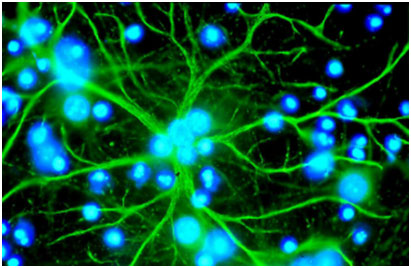

一項新的研究發(fā)現(xiàn),大腦中的星形膠質(zhì)細(xì)胞可能是癌細(xì)胞腦轉(zhuǎn)移的“幫兇”。

星形膠質(zhì)細(xì)胞